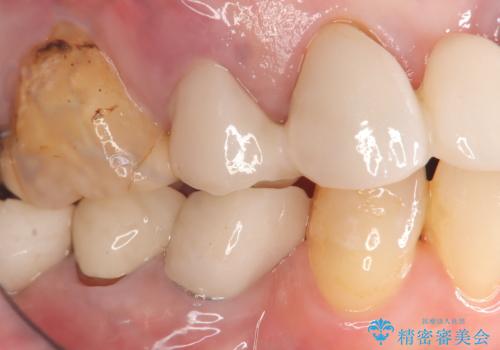

歯の破折 食べる喜びが蘇るインプラント治療